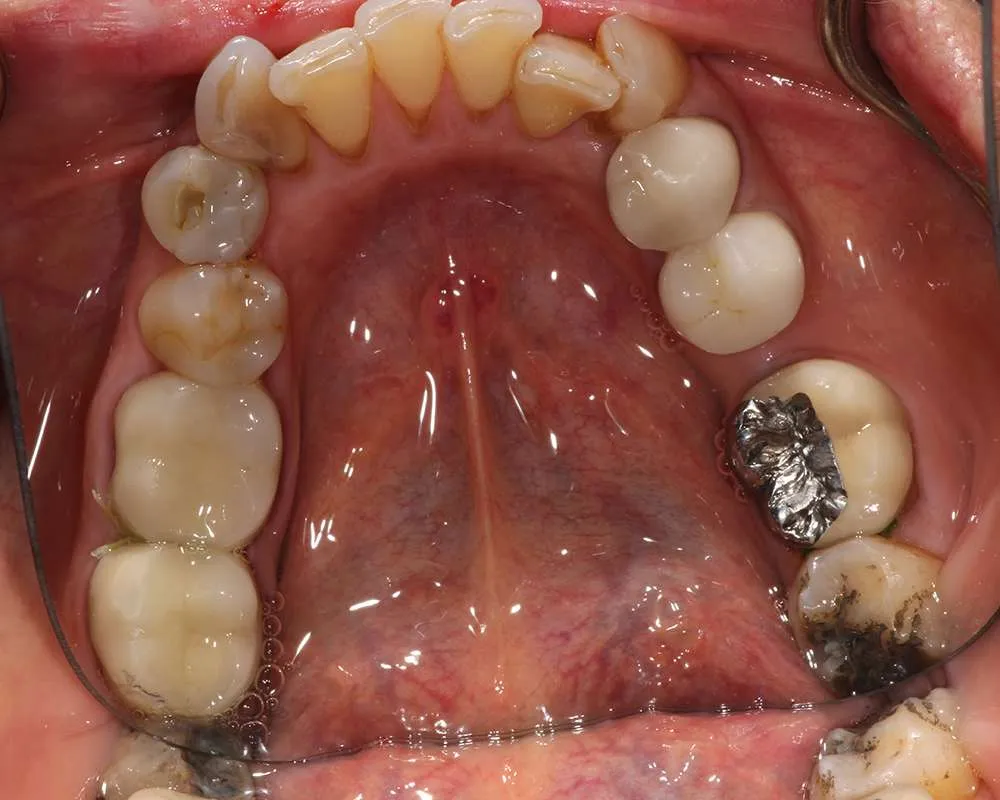

Real Stories, Real Results: Case Studies Showcasing How Our Personalized Approach Transforms Smiles and Lives

Complex Cases

Witness the Remarkable Changes We Can Achieve

The safe removal of mercury fillings is crucial for your health and well-being. At our practice, we follow strict protocols to ensure that mercury amalgam fillings are removed safely and effectively.